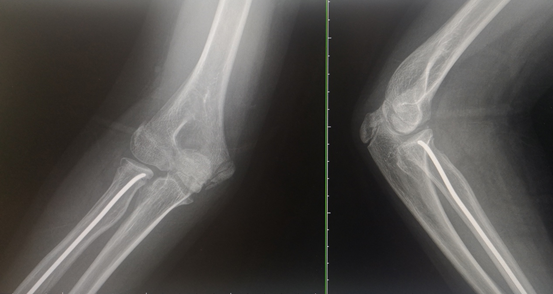

患儿,女,11岁,5月14日因“外伤后右肘肿痛1小时余”入院,术前X线提示右侧桡骨颈骨折,O’Brien分型Ⅱ型,入院后我科陈义权主任立即和张浩医生采用中医特色骨折夹板固定骨折处,于5月17日予右桡骨颈骨折闭合复位弹性髓内钉内固定术,术中我科陈义权主任采用Metaizeau技术,在腕部做一长约1cm切口,利用弹性髓内钉闭合复位骨折端。术后3月复查,骨折端基本愈合。我科成功将中医特色治疗与小儿骨折微创治疗技术完美结合。

图5、6:术后2月、3月骨折X线片,示骨折愈合良好